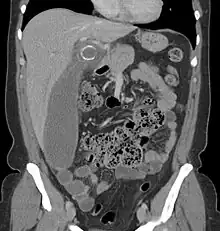

Computed tomography

Where it is readily available, computed tomography (CT) has become frequently used, especially in people whose diagnosis is not obvious on history and physical examination. Although some concerns about interpretation are identified, a 2019 Cochrane review found that the sensitivity and specificity of CT for the diagnosis of acute appendicitis in adults was high.[63] Concerns about radiation tend to limit use of CT in pregnant women and in children, especially with the increasingly widespread usage of MRI.[64][65]

The accurate diagnosis of appendicitis is multi-tiered, with the size of the appendix having the strongest positive predictive value, while indirect features can either increase or decrease sensitivity and specificity. A size of over 6 mm is both 95% sensitive and specific for appendicitis.[66]

However, because the appendix can be filled with fecal material, causing intraluminal distention, this criterion has shown limited utility in more recent meta-analyses.[67] This is as opposed to ultrasound, in which the wall of the appendix can be more easily distinguished from intraluminal feces. In such scenarios, ancillary features such as increased wall enhancement as compared to adjacent bowel and inflammation of the surrounding fat, or fat stranding, can be supportive of the diagnosis. However, their absence does not preclude it. In severe cases with perforation, an adjacent phlegmon or abscess can be seen. Dense fluid layering in the pelvis can also result, related to either pus or enteric spillage. When patients are thin or younger, the relative absence of fat can make the appendix and surrounding fat stranding difficult to see.[67]